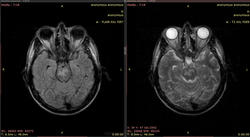

Видны изменения в стволе мозга (мост), белом веществе мозжечка и, помимо этого, белом веществе большого мозга (виден по крайней мере один перивентрикулярный очаг в левой теменной доле, нельзя исключить более мелких очагов - трудно судить по низкопольным картинкам).

Такая картина характерна для центрального понтинного миелинолиза. Он возникает в основном у алкоголиков на фоне острый осмотических нарушений. При этом поражается в основном мост, но также могут быть видны очаги в других отделах мозга (экстрапонтинный миелинолиз). Поэтому и понтинные, и экстрапонтинные изменения объединяются термином "синдром осмотической демиелинизации". Вот здесь разные случаи: http://radiopaedia.org/articles/central-pontine-myelinolysis

Второй вариант, менее вероятный - первичное демиелинизирующее заболевание (РС).

C учетом наличия очагов в мозжечке и перивентрикулярно - скорее РС.

Наверное, вы правы. В продолговатом мозге тоже очаги.